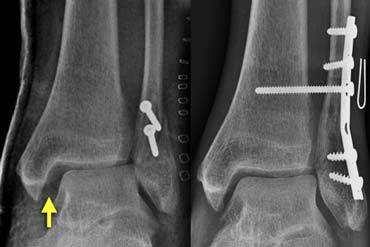

The case on the left shows a Weber B fracture.

On these images the ankle fork is normal.

Both the medial and lateral clear spaces are prominent, but within normal limits.

We can conclude that there is no dislocation, but we do not know if there is rupture of the medial collateral ligaments or of the syndesmosis.

Continue with the images post surgery.

Following osteosynthesis there is obvious widening of the medial and lateral clear spaces (image on the far left).

This indicates that there is a syndesmotic rupture and medial collateral ligament rupture.

The ring is still broken in two places.

The ankle joint is unstable and dislocated.

Resurgery was necessary with placement of a syndesmotic screw to stabilize the ankle joint.

Stability (6)

On the left another case. There is a Weber B fracture.

Both the medial and lateral clear spaces are widened, indicating instability.

The talus is displaced laterally.

Patient was scheduled for osteosynthesis of the fibular fracture and placement of a syndesmotic screw if necessary.

After osteosynthesis of the fibula, the ankle was tested in the operating room and found to be stable.

There was no indication for a syndesmotic screw.

It was concluded that the syndesmosis was only partially ruptured, as is usually the case in Weber B fractures.

The ring was broken in two places and after repairing one of them, the ring was stable.